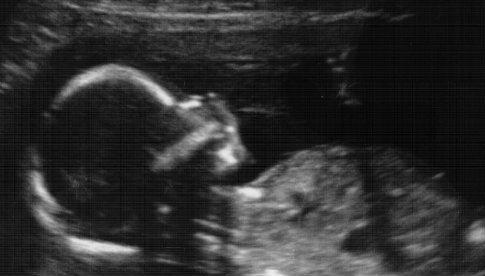

And then 10% of the time, I'm afraid. Sometimes deeply afraid. I've had lots of uterine sensations this week. I usually feel something once or twice a week, but this week it's been pretty much every day at some point. Sometimes just an odd feeling, sometimes a uterine tightening. Sometimes a stabbing vaginal pain, although that's been momentary. It's been hard not to get scared that something is wrong. That my cervix is giving way, that something is wrong with the baby. So I went in this week to get checked. Baby looked much the same as last week, slumped over with the weight of her ginormous, heavy head. The OB checked my cervix also, and she said it was fine. So that was reassuring, although I am still a little nervous.